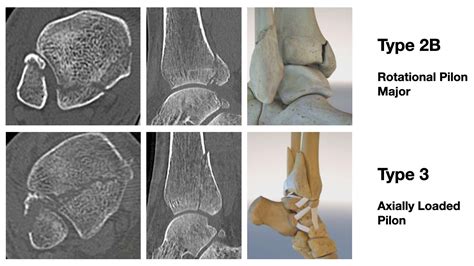

CT Scan Indispensable for assessing the size of the later shard and the degree of articulary surface engagement.

The approach to treatment bet largely on the sizing of the sherd and the constancy of the ankle juncture. Not all break involve or, but when the sherd involves more than 25 % of the tibial articulary surface or if the ankle remains unstable, operative interference is broadly the touchstone of attention.

For displaced fault or those involve a big articulary surface, surgery (Open Reduction Internal Fixation - ORIF) is ordinarily execute. The goals of surgery are to reconstruct the joint surface, fix the crushed bones using screws or plates, and stabilize the ankle ligaments.